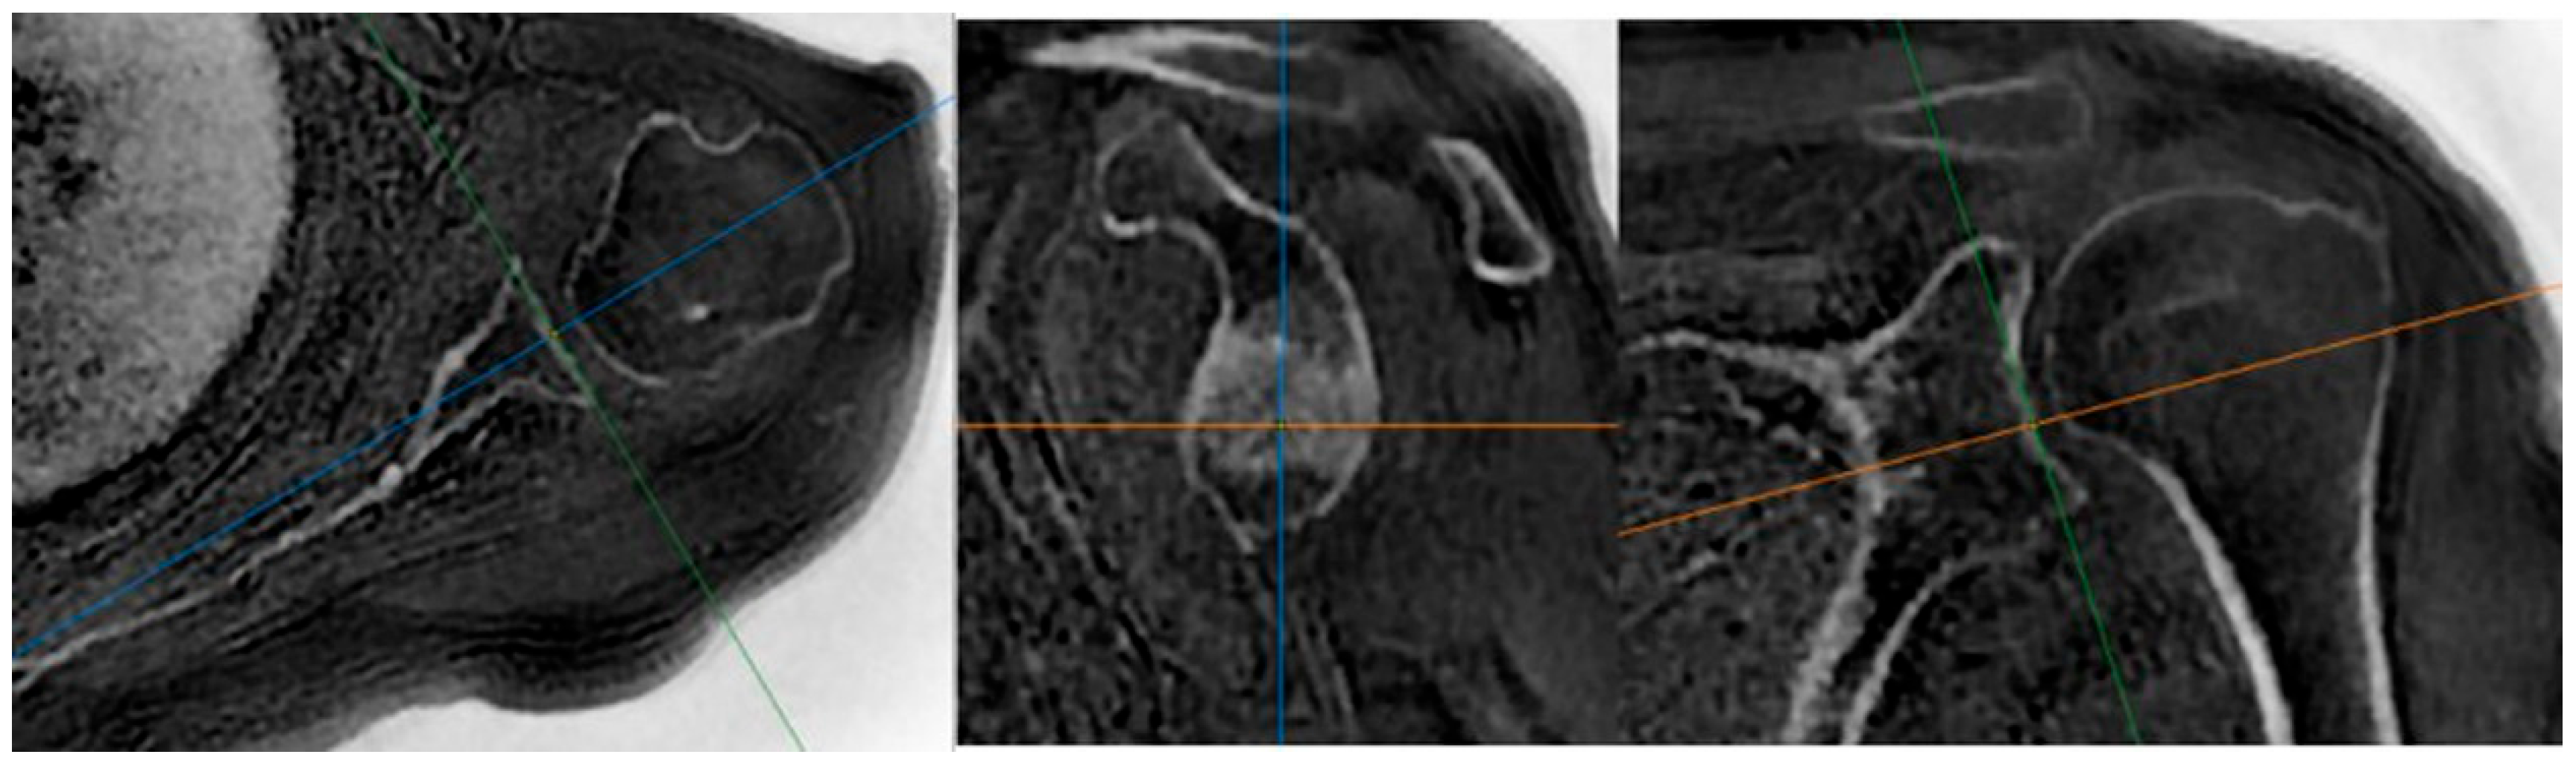

- MRI-based measurements